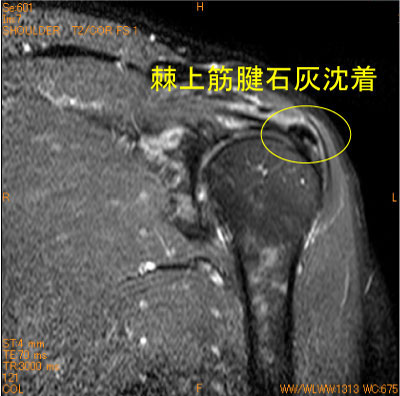

石灰沈着腱板炎-肩関節MRI-

60代男性。ゴルフ時の疼痛肩。

MRI撮影時に必ずしも石灰沈着が指摘されている訳ではない。

常日頃、筋内腱のlow signalの走行、大きさを脳裏に焼き付けておいて、異常なlow signalの存在に気がつく必要がある。

![]() Obl. Cor T2WI 脂肪抑制 |